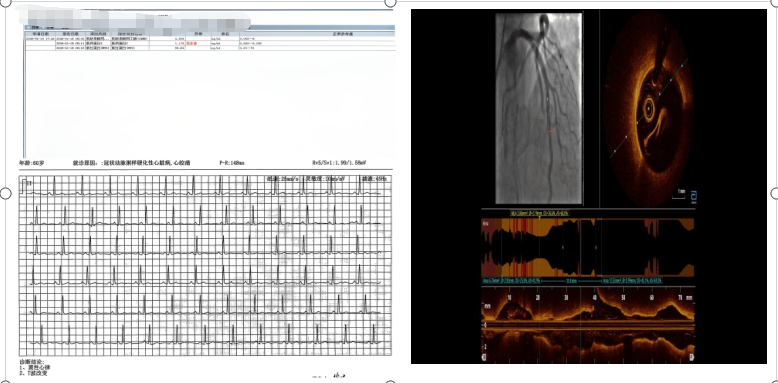

转至新桥医院后,科室赵晓辉主任第一时间带领医疗团队为患者开展全面评估。检查结果显示,患者心肌损伤标志物显著升高,心电图也明确提示心肌梗死,但紧急冠脉造影检查却发现,其主要血管并无超过50%的严重狭窄——这一结果与此前当地医院的检查结论、患者典型的心肌梗死症状形成鲜明矛盾,诊疗工作一度陷入僵局。不过,患者夜间仍频发静息胸痛,需舌下含服硝酸甘油才能缓解,这一关键症状让医疗团队坚定了深入探究、破解病因的决心。

为破解诊断迷雾、明确病因,医疗团队再次为患者实施冠脉造影,并创新性联合高分辨率光学相干断层成像(简称OCT技术,一种精准观察血管内部病变的先进检查方式)进行精准检查,最终成功锁定病因——患者冠状动脉前降支远段存在肌桥合并斑块破裂,据此确诊为非阻塞性冠状动脉心肌梗死(MINOCA,“隐形心梗”)。据悉,MINOCA是一种特殊类型的心肌梗死,约占所有心梗病例的5%-10%,尤其在中青年、女性及无典型危险因素人群中易发生漏诊。其核心特征是,患者虽有明确的心肌梗死表现,但冠脉造影未发现明显阻塞性病变,因此常被误判为“假心梗”或其他疾病。